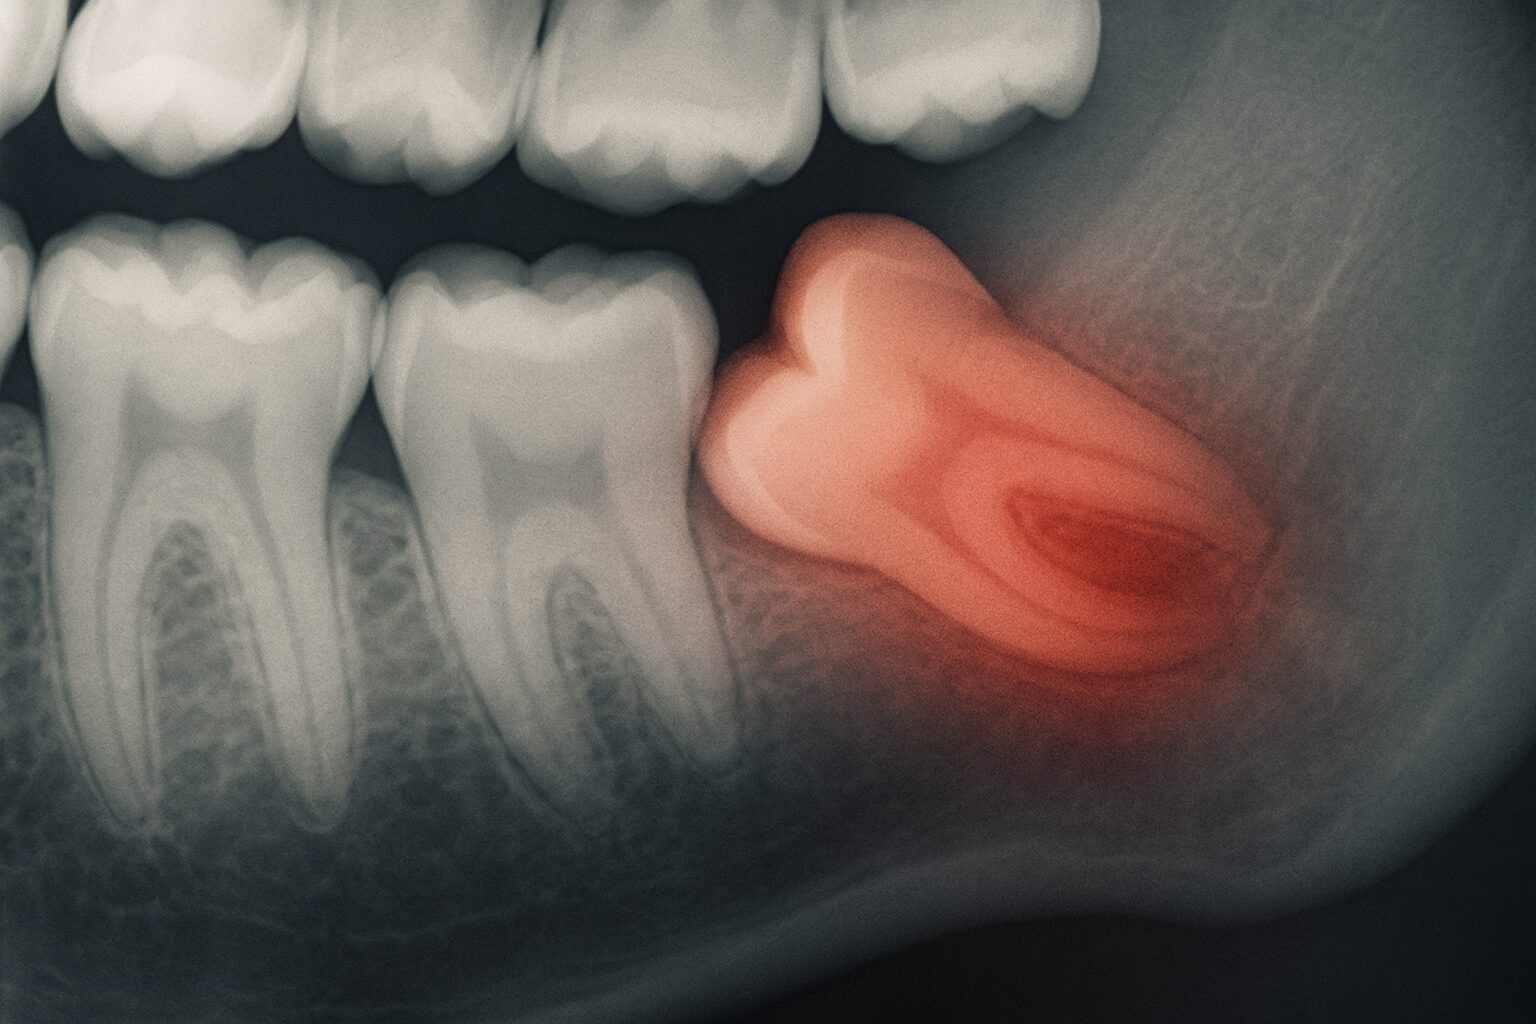

Ząb mądrości, znany również jako ósemka, to ostatni ząb trzonowy wyrzynający się w łukach zębowych, zazwyczaj między 17 a 25 rokiem życia. Często brakuje dla niego miejsca, co prowadzi do problemów. Ósemki mogą być zatrzymane w kości, częściowo wyrżnięte lub rosnąć w nieprawidłowej pozycji, powodując dyskomfort i komplikacje wymagające interwencji chirurgicznej.

Przygotowanie do zabiegu chirurgicznego usuwania ósemek w Warszawie rozpoczyna się od konsultacji ze stomatologiem lub chirurgiem stomatologicznym. Podczas wizyty specjalista oceni położenie ósemek, wykona zdjęcia rentgenowskie, aby zaplanować zabieg. Pacjent zostanie poinformowany o przebiegu ekstrakcji, potencjalnych powikłaniach i zaleceniach pozabiegowych.